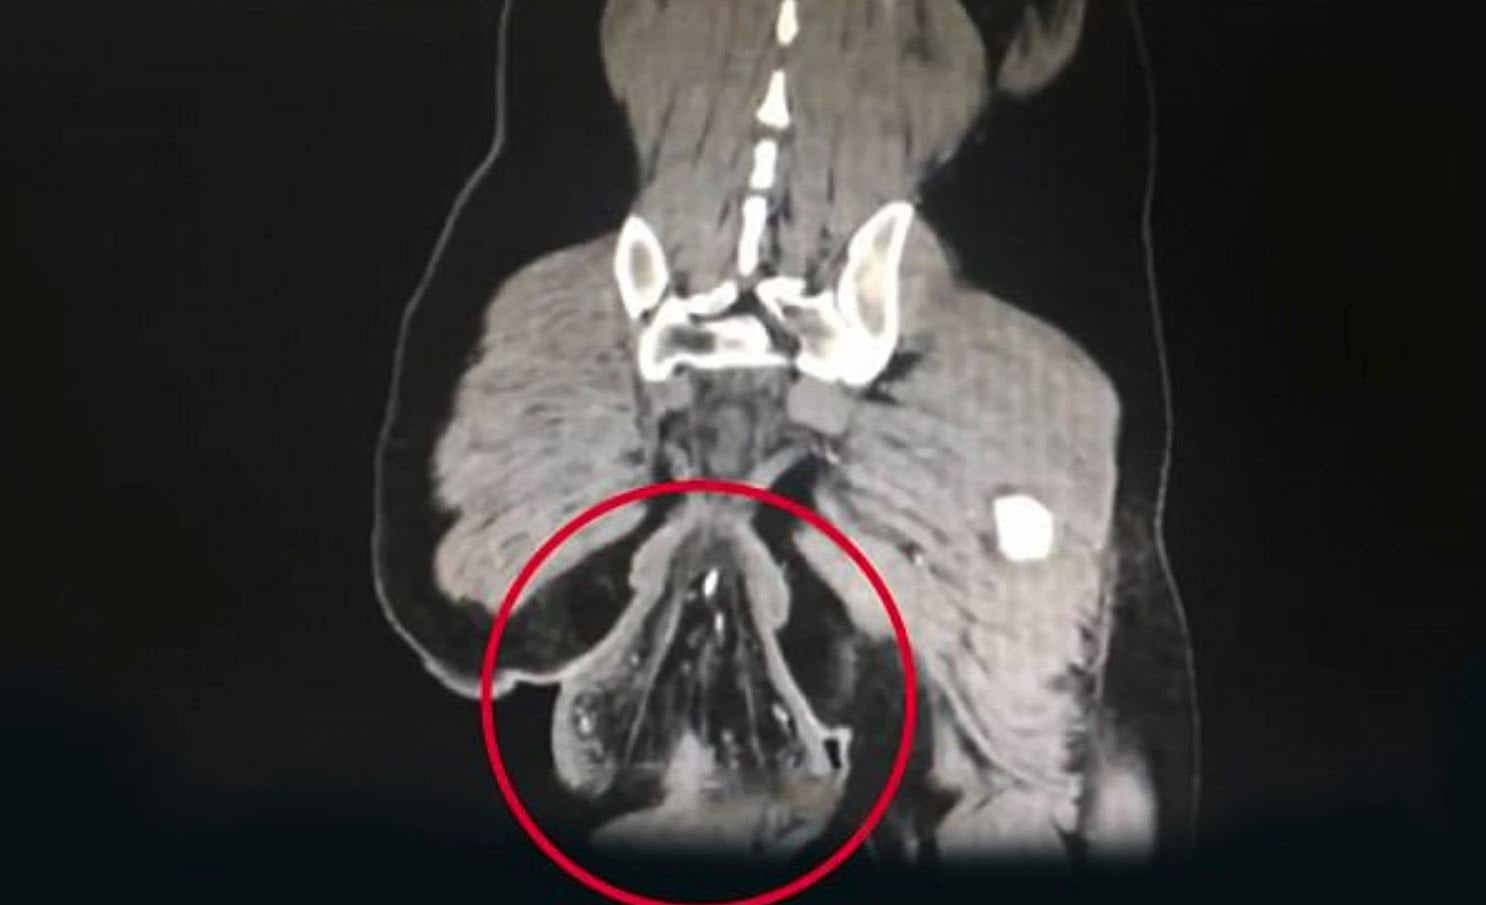

Düşen organın ne olduğunu bilmeyen ve yardım ekiplerine giden adam acil servise kaldırıldı. Doktorlar röntgen ve incelemelerini tamamladıktan sonra adamın vücudunda sallanan parçanın rektum olduğunu açıkladı. Kalın bağırsağın son bölümü olarak da bilinen rektumun vücuttan düştüğünü röntgenden anladıklarını duyururken, "Rektum vücuttan kopmuş. Bunun sebeplerinden biri adamın uzun süreler boyunca tuvalette oturması ve bu süre boyunca telefonuyla oyun oynamasıdır" açıklamasını yaptı.

Yapılan incelemeler sonucunda adamın anüsünden çıkan 16 santimetre çapındaki organın rektum olduğu belirlendi. Yapılan incelemeler sonucunda adamın anüsünden çıkan 16 santimetre çapındaki organın rektum olduğu belirlendi.